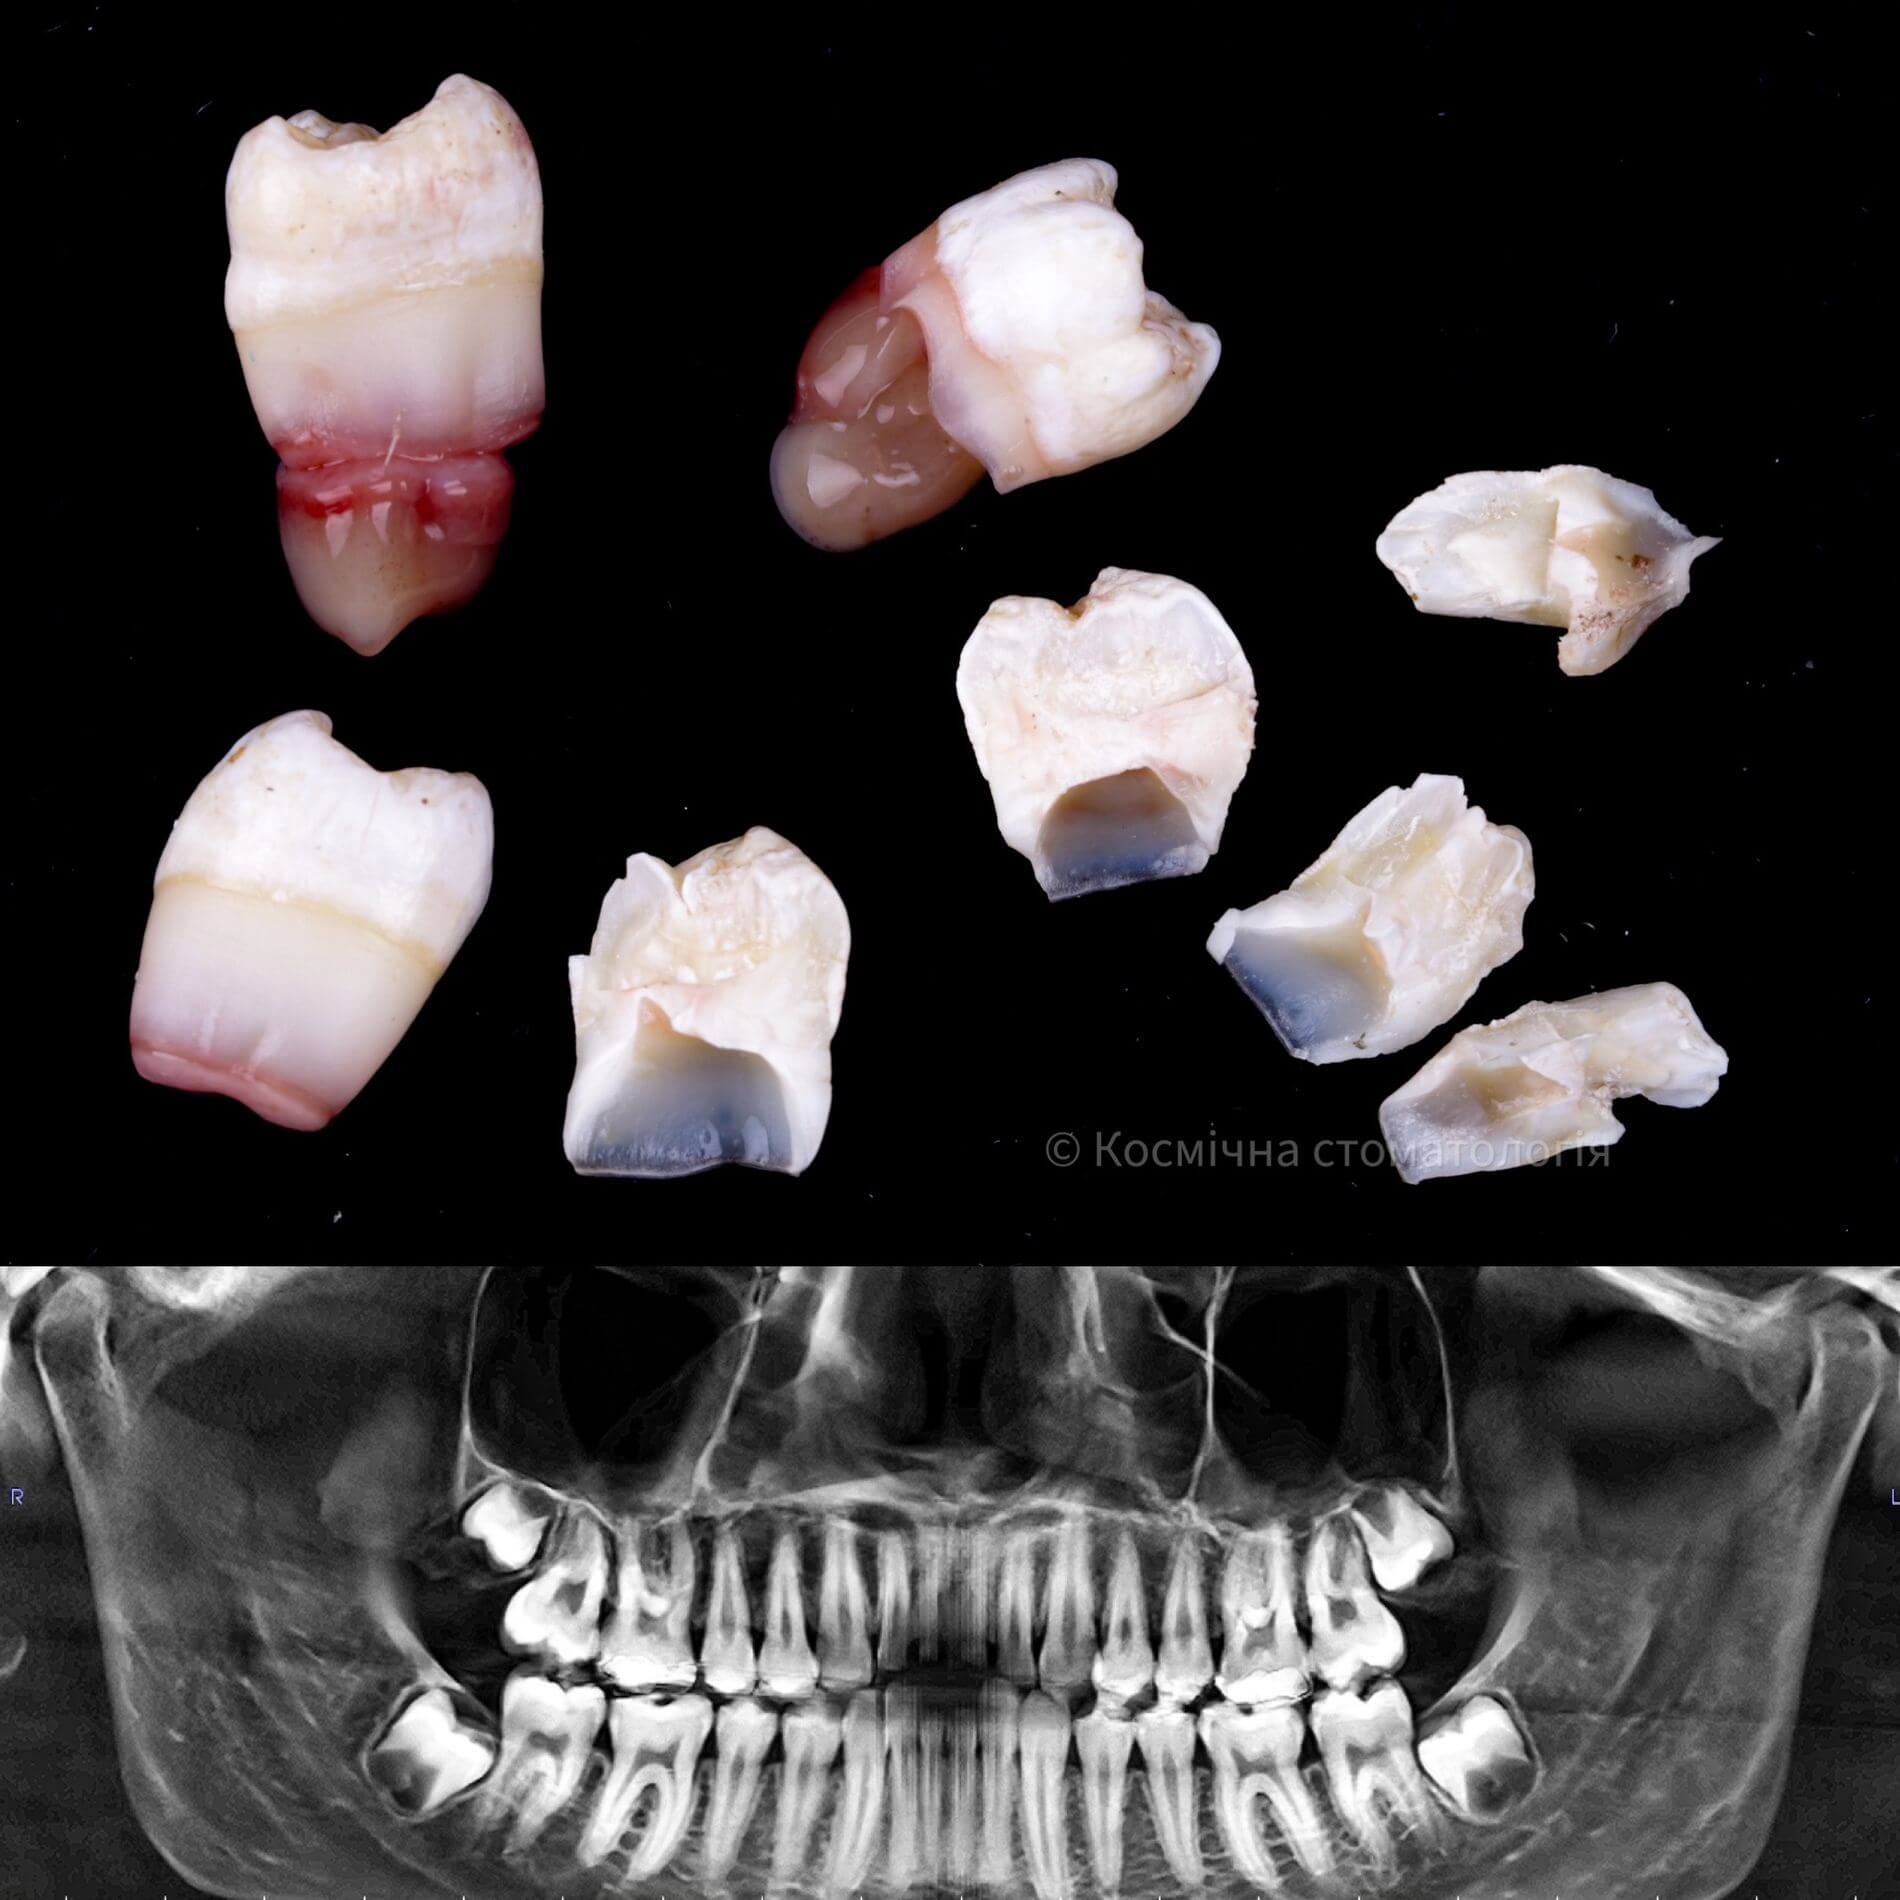

• Полное удаление зуба - если зуб полностью прорезался и имеет сросшиеся корни.

• Отдельное удаление коронки зуба и его корней - если зуб прорезан и корни растут по отдельности.

• Удаление зуба по схеме 1 или 2 с разрезом десен - если зуб прорезан частично.

• Разрез десен, освобождение зуба от близлежащей кости ультразвуком и удаление по схеме 1 или 2 - если зуб не прорезался, но беспокоит.

Вырвать зуб мудрости во Львове можно проще, чем тебе кажется, в Космической стоматологии Драганчука. Начни этот путь с простого шага - первичной встречи с хирургом-стоматологом. На консультации мы сделаем основное - направим тебя на 3D компьютерную томографию, чтобы учесть близость нижнечелюстного нерва (нижние 8-ки) и верхнечелюстной пазухи (верхние 8-ки) и составим план удаления зубов.

Вырвать зуб мудрости во Львове можно проще, чем тебе кажется, в космической стоматологии Драганчука. Начни этот путь с простого шага – первичной встречи с хирургом-стоматологом. На консультации мы сделаем основное – направляем тебя на 3D компьютерную томографию, чтобы учесть близость нижнечелюстного нерва (нижние 8-ки) и верхнечелюстной пазухи (верхние 8-ки) и составим план удаления зубов.